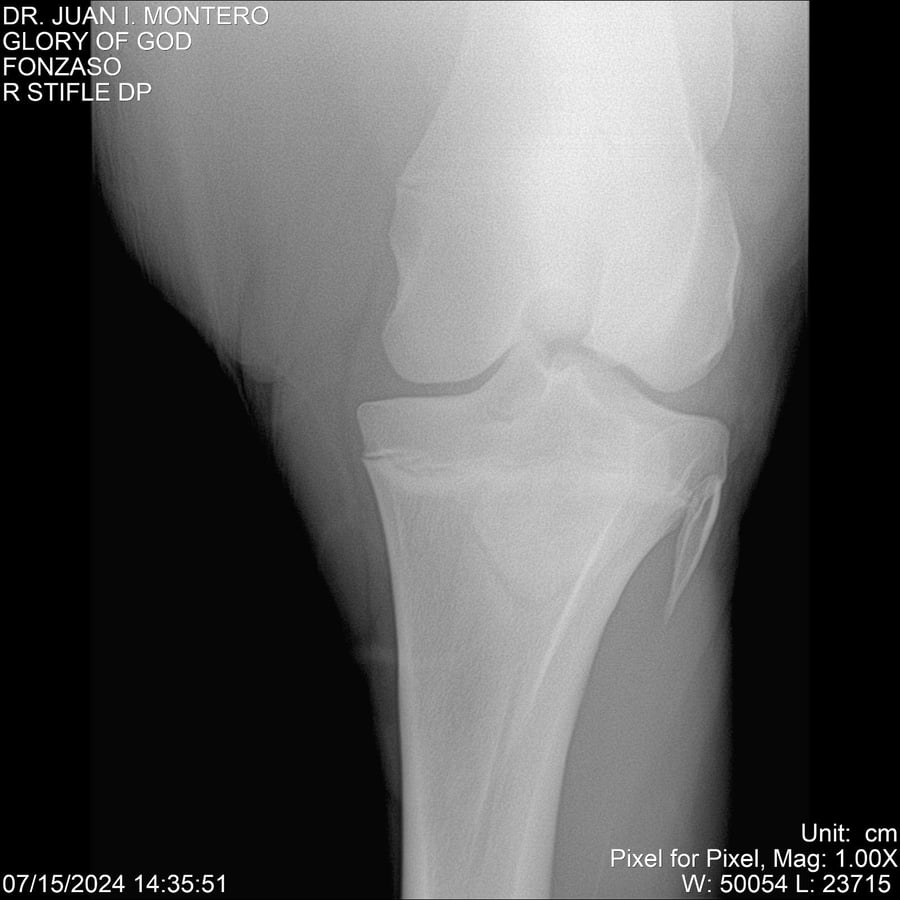

LOTE 10, GLORY OF GOD 🔥 🔥 🔥 Lote Anterior Volver al remate Lote Siguiente Ficha Contacto Montevideo - Ficha del Lote Identificador: #281389 Categoría: Yeguarizos Montevideo - 115 Visualizaciones ClicData Contacto Empresa: Abelenda N. R., Walter Hugo Nombre*: Teléfono* : E-mail* : Mensaje Enviar Registrese gratis Este contenido Exclusivo está disponible sólo para usuarios registrados Ingresar